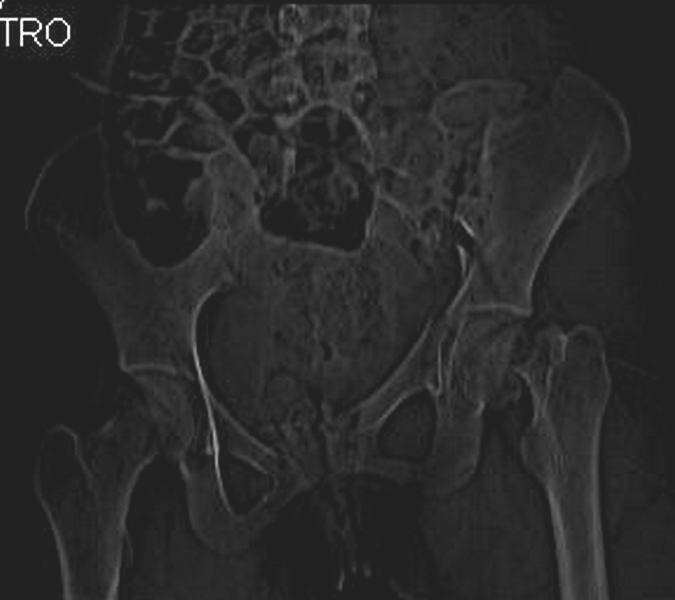

Уважаемые коллеги! С прошедшеми Вас праздниками. Теперь ближе к трудовым будням. Поступила 16 летняя девушка неделю назад. Механизм травмы падение с 5 этажа. Краткий диагноз:закрытый перелом левой ключицы, левого плеча, закрытый вертикально и ротационно нестабильный перелом костей таза:закрытый перелом левой подвздошной кости, переломы лонной кости справа, перелом обоих колонн вертлужной впадины слева;субкапитальный перелом шейки левой бедренной кости со смещением. По тактике лечения таза возникли следующие вопросы: 1. С чего начать - фиксации переломов вертлужной впадины или устранения деформаций таза? 2. Надо ли фиксировать шейку или фиксировать бедро в аппарате вместе с тазом, а после сращения таза планировать ТЭП ТБС? Если имеются еще какие подводные камни, будем рады выслушать.Спасибо.

Перелом шейки смогли зафиксировать через пару дней, ацетабулум до сих пор не оперирован, на вытяжении.

Из-за упущенного времени (три недели с момента

поступления) ацетабулум ведем консервативно.

На снимке ацетабулума редко встречающийся очень низкий перелом, наверное, трудно было репозицию через один доступ? Перелом как бы замкнулся в квадрилатеральной поврехности.

Ничего такого особенного в переломе вертлужной впадины не опознал. Транстектальный перелом хорошо репонируется щипцами, установленными через седалищную вырезку.

В положении на спине подвздошным и надлобковым доступом восстанавливается тазовое кольцо, фиксация пластинами. При хорошей репозиции может улучшиться конгруэнтность в суставе.

Затем, если положение хорошее, закрытый остеосинтез шейки винтами.

Если нет - в положении на боку, синтез задней колонны из наружно-латерального доступа и синтез головки винтами, но уже под визуальным контролем.

На картинке подобный случай, только без шейки, сделано через месяц или полтора после травмы.